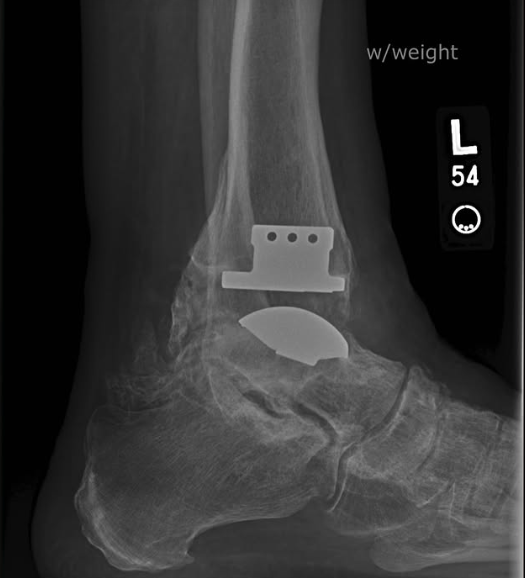

Dolph Lundgren, la leyenda del cine de acción que interpretó a Ivan Drago en Rocky IV y a He-Man en Masters of the Universe, ha compartido detalles impactantes sobre las secuelas físicas de su larga carrera. A través de sus redes sociales, el actor sueco de 68 años publicó una radiografía de su tobillo izquierdo, donde se observa claramente una placa metálica y tornillos insertados entre los huesos, resultado de cirugías previas.

“En caso de que hayas notado mi ligera cojera. Mi tobillo izquierdo es como un pedazo de hierro después de 50 años de artes marciales y 100 películas de acción. Al menos no hay dolor, así que todavía puedo patear”, escribió Lundgren en Instagram, acompañando la imagen con humor y resiliencia.